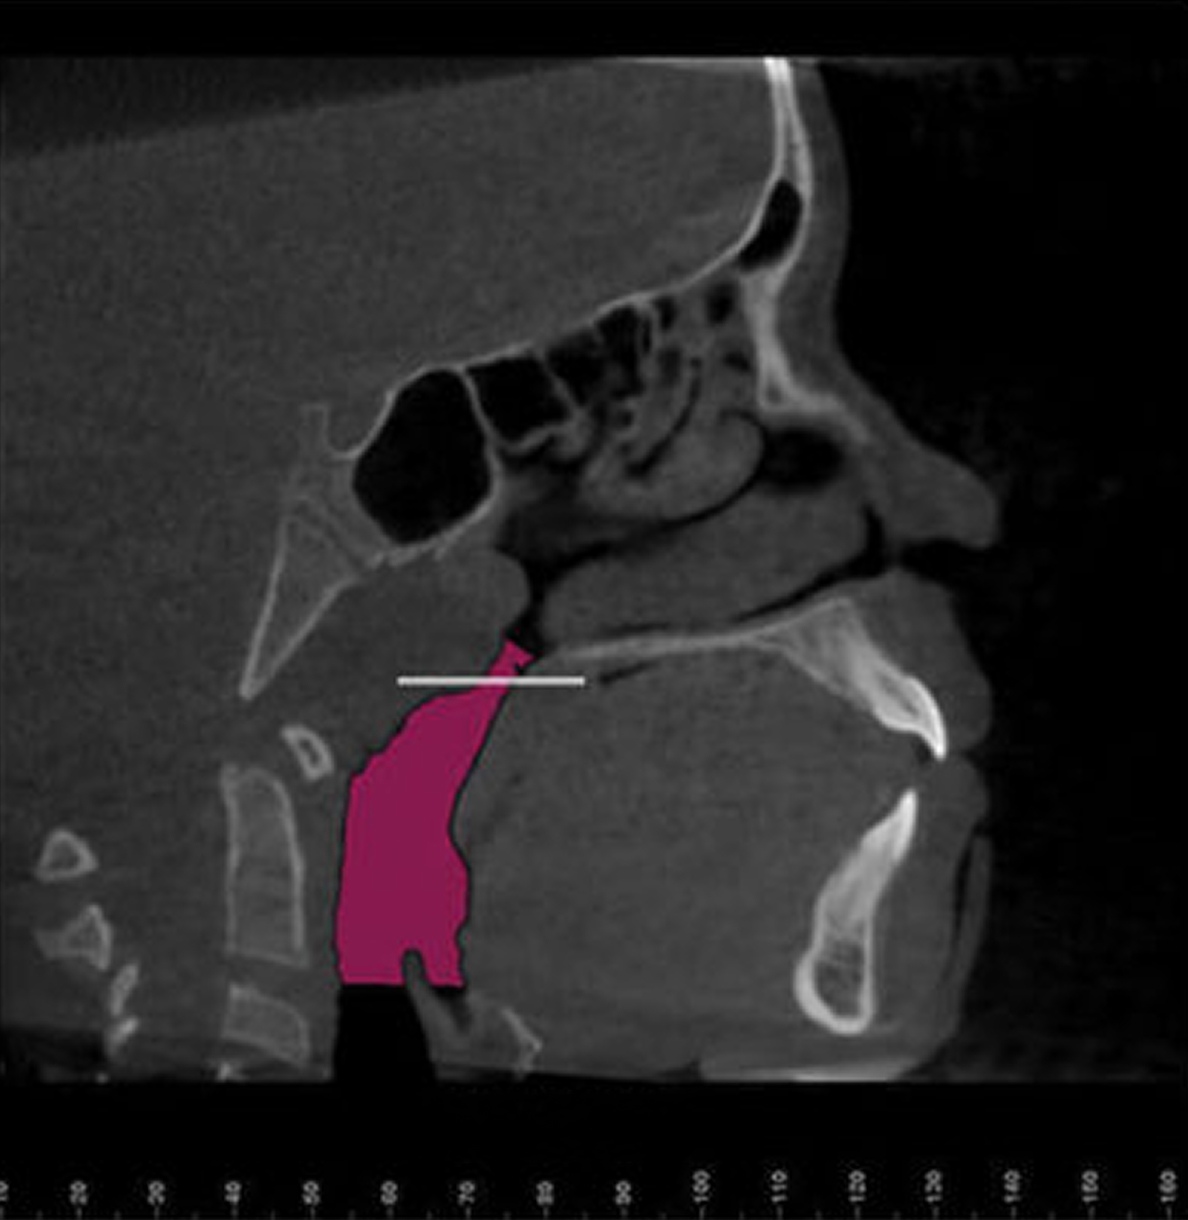

For many patients, an orthodontic intervention in Highland, NY or Ramsey, NJ can improve and sometimes eliminate these risks. Below are pictures of an OSA patient that benefitted from orthodontic treatment’s life-changing effects at Van Vliet & Ganz Orthodontics.

867% Airway Enhancement